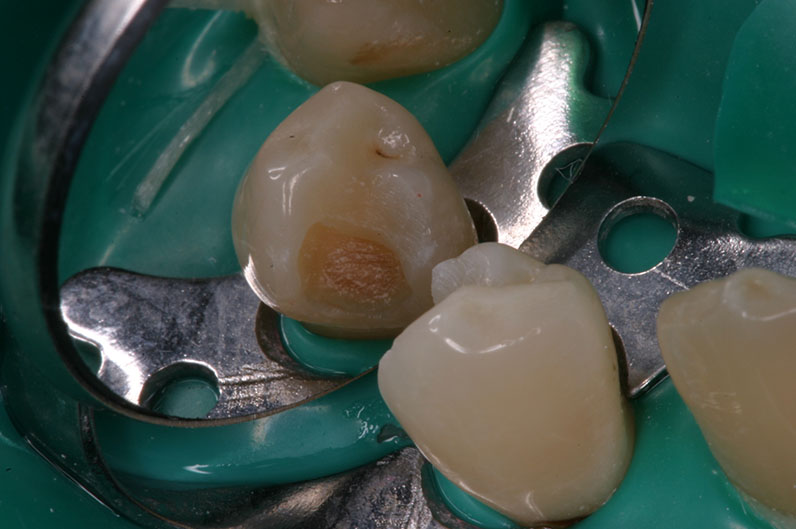

nach Exkavation

mit Proface*

ohne Proface*

ohne Proface